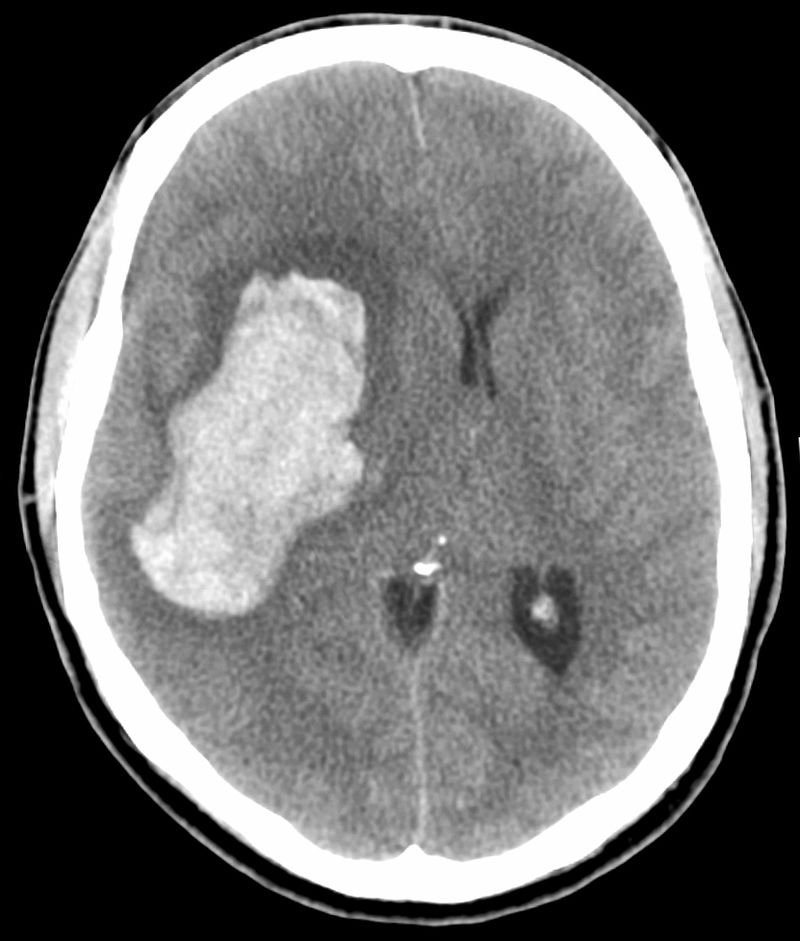

My folks were forced to live their own separate lives ever since the night my dad suffered a major stroke when I was 14 years old. My parent’s drawn-out tragic drama existed as a backdrop to my existence for the next 18 years of my life, and I always struggled with how to deal with the horrors of critical illness. My mom never fared well since the night her husband lost his mental capacities, and as a result, she lost her grip on her mental faculties as well. Mental illness was a disease that I was forced to get intimate with, and I’d be lying if I didn’t admit that I didn’t handle living with my mother very well. Ours was a strained relationship, and I often pushed her away when I should have drawn her close. I didn’t deal with the situation of my father being in a nursing home any better, and I openly admitted that I hated visiting him because he never seemed to care whether I was in the room with him or not. Brain damage is a curious thing, and I never found it curious in a positive way. I could only see the negative effects of what losing half of one’s brain looked like, and it often made me angry that someone could be so injured yet remain so perfectly alive.